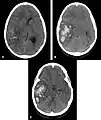

- Hémorragie cérébrale : la principale manifestation clinique de l'angiopathie amyloïde est l'hémorragie intracérébrale de topographie lobaire ou cérébelleuse[7]. La topographie lobaire regroupe les structures corticales et sous-corticale (c'est-à-dire proche de la surface du cerveau). Elle est principalement définie par opposition à la topographie profonde qui englobe essentiellement les ganglions de la base (en particulier le thalamus ou le noyau lenticulaire) et le pont. Cette distinction topographique est importante dans la mesure où l'hémorragie cérébrale lobaire est très évocatrice d'AAC alors que l'hémorragie cérébrale profonde est plutôt évocatrice de microangiopathie hypertensive. Cette distribution reflète l'atteinte préférentielle des petits vaisseaux corticaux dans l'AAC et de artères lenticulo-striées dans l'angiopathie hypertensive[8]. Cependant, parmi l'ensemble des topographies lobaires possibles, l'atteinte du lobe temporal ou occipital semble prédominante, en particulier si le patient avait déjà présenté une hémorragie dans ces régions[9]. Comme pour l'ensemble des AVC, les symptômes associés aux hémorragies cérébrales de l'AAC sont variables. Ils dépendent avant tout de la taille de l'hémorragie et de sa localisation.

Scanner cérébral objectivant une hémorragie lobaire temporale droite évocatrice d'une possible angiopathie amyloïde Scanner cérébral objectivant une hémorragie lobaire temporale droite évocatrice d'une possible angiopathie amyloïde

Scanner cérébral objectivant une hémorragie profonde (thalamique gauche) plutôt évocatrice d'une angiopathie hypertensive Scanner cérébral objectivant une hémorragie profonde (thalamique gauche) plutôt évocatrice d'une angiopathie hypertensive